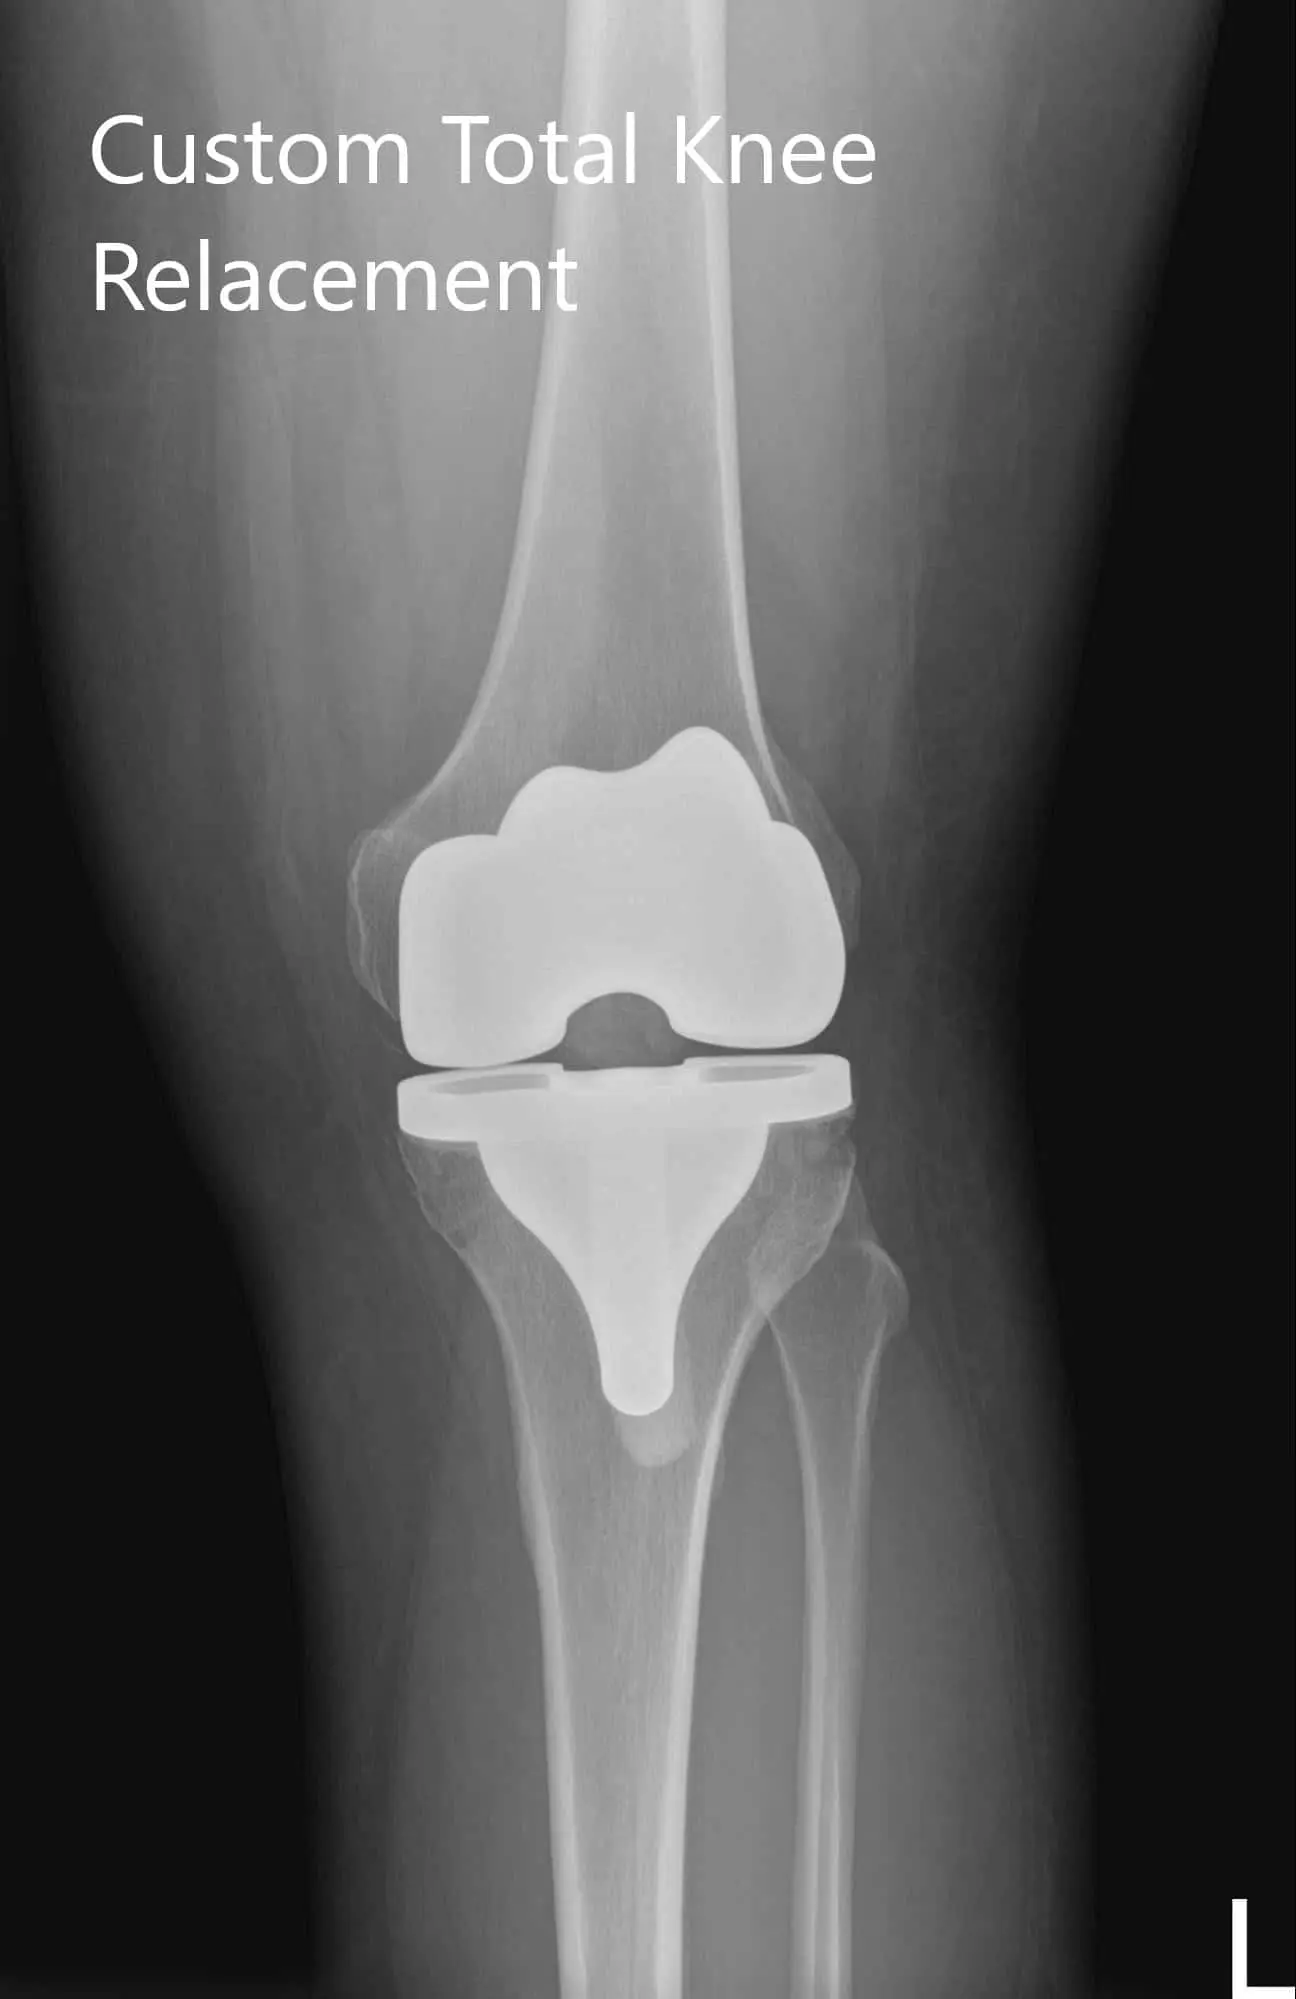

Postoperative X-ray of the left knee showing AP and lateral image

Postoperative X-ray of the left knee showing AP and lateral images - img 2

Postoperative X-ray of the left knee showing AP and lateral images

The patient was ambulatory the same day of the surgery. He reported well control of pain with medications and had a good range of motion about the left knee. The patient’s wound was clean, dry and intact. He had excellent compliance with physical therapy and home exercise program. He reported no pain (0/10) and an excellent range of motion after 3 months.